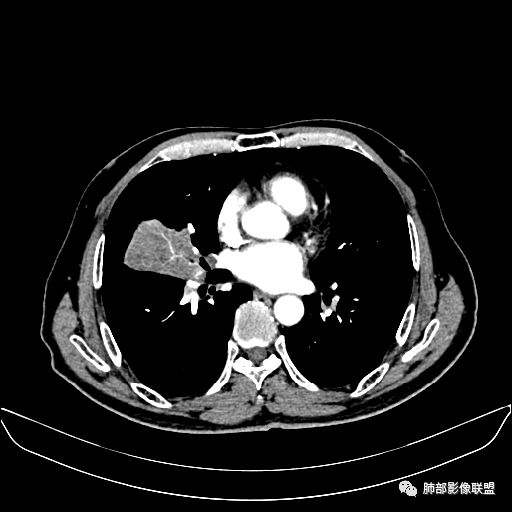

入院CT

老年男性,因“咳嗽咳痰1月余。”入院。病程中咳嗽咳痰,咳黄白痰,间断咯少许鲜红色痰血。PPD阳性。胸CT:右肺中叶外侧段支气管管腔阻塞,大片实性病变,病灶边缘光滑,部分边缘膨隆,可见分叶,肺门及纵隔可见肿大淋巴结,并可见钙化。增强可见病灶明显强化,而且延迟强化明显,病灶内多发低密度区,内见血管影,血管变细、部分血管破坏。考虑恶性病变可能性大,鉴别慢性肉芽肿性病变。

右肺中叶外侧段管腔阻塞、实性病变,病灶边缘光滑,可见分叶,肺门及纵隔可见肿大淋巴结,并可见钙化。增强可见病灶内多发低密度区。

老年男性,咳嗽、咳痰1月余,间断血痰。PPD阳性。

胸CT:跨叶大肿块,主体在中叶,右中叶外侧段支气管阻塞,病灶部分边缘膨隆,可见分叶,部分边缘平直,肺门及纵隔可见肿大淋巴结。增强病灶不均匀强化,延迟强化明显,病灶内多发低密度区,内见血管飘浮,部分血管变细、模糊。考虑:恶性病变可能性大,大细胞?淋巴瘤?鉴别慢性肉芽肿性病变。